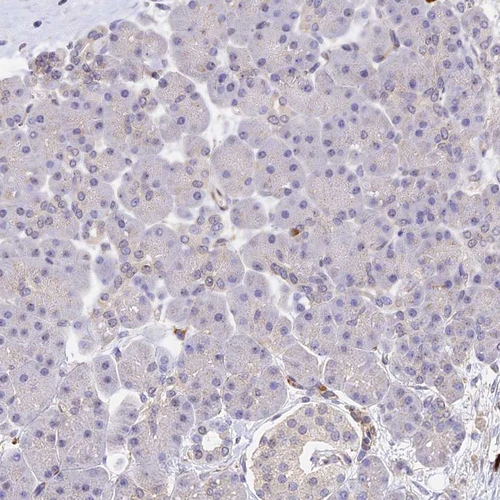

Immunohistochemical staining of human lymph node shows strong membranous and cytoplasmic positivity in germinal and non-germinal center cells.